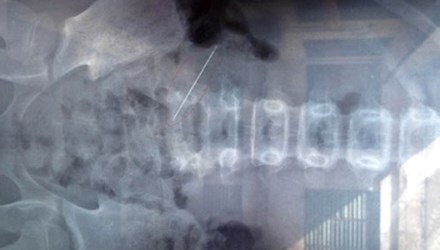

Chiếc kim nằm 8 tháng trong mông bệnh nhân được bác sĩ lấy ra. Ảnh: Vietnamnet |

Kết quả chụp X-quang phát hiện một chiếc kim khâu quần áo nằm sâu trong mông trái của bệnh nhân. Sau khi làm các xét nghiệm và hội chẩn, bệnh nhân được chỉ định phẫu thuật lấy dị vật.

Chiếc kim lấy ra là kim khâu quần áo, đã hoen gỉ. Hiện bệnh nhân đã ổn định và được xuất viện.